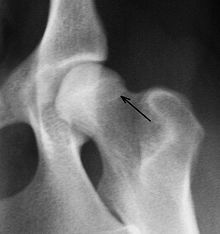

Eine zuverlässige Möglichkeit, den Schweregrad der Erkrankung zu erkennen, ist die Röntgenuntersuchung. Dabei müssen die Gelenke überstreckt werden, was beim Vorliegen einer HD starke Schmerzen verursacht. Daher wird sie unter Kurznarkose durchgeführt. Voraussetzung für eine aussagekräftige Diagnose ist die exakte Positionierung des Tieres in Rückenlage mit gestreckten, parallel gelagerten Oberschenkeln und rechtwinklig zum Strahlengang eingedrehten Kniescheiben. Die ordnungsgemäße Lagerung kann anhand der Form der Foramina obturatoria, der Form der Darmbeinschaufeln, der Breite der Darmbeinsäulen und der Position der Kniescheiben beurteilt werden. Zusätzliche Aufnahmen können in „Froschhaltung“ der Oberschenkel oder im seitlichen (latero-lateralen) Strahlengang erfolgen, in Deutschland wird dies nur bei Obergutachten durchgeführt.

Röntgenaufnahme einer HD beim Hund. Der Femurkopf ist bereits subluxiert, das Acetabulum (Hüftgelenkspfanne) umgreift ihn nicht mehr (rote Pfeile). Die Femurköpfe zeigen Abweichungen von der Halbkugelform (gelbe Pfeile); rechts im Bild sind deutliche arthrotische Veränderungen des Femurkopfes erkennbar.